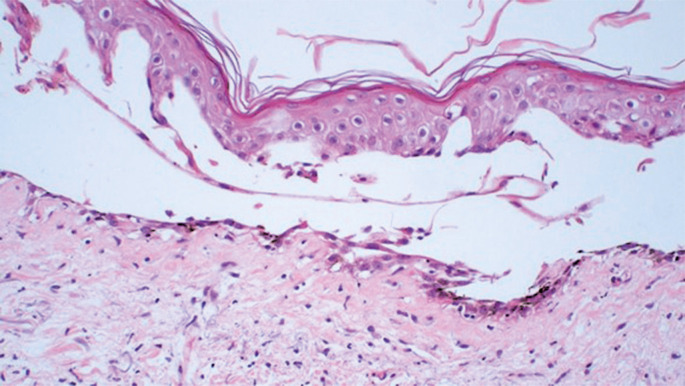

Azacitidine-induced bullous pemphigoid-like localized toxic reaction.

Azacitidine is a hypomethylating agent recommended for the treatment of patients with high-risk myelodysplastic syndromes. Here, we report the case of a patient with myelodysplastic syndrome who was not eligible for allogeneic stem cell transplantation (allo-SCT) and presented with a rare and previously unreported cutaneous side effect after the use of subcutaneous azacitidine. We propose that changing the route of azacitidine administration from subcutaneous to intravenous could potentially decrease the occurrence of bullous pemphigoid-like localized toxic reactions in some patients.